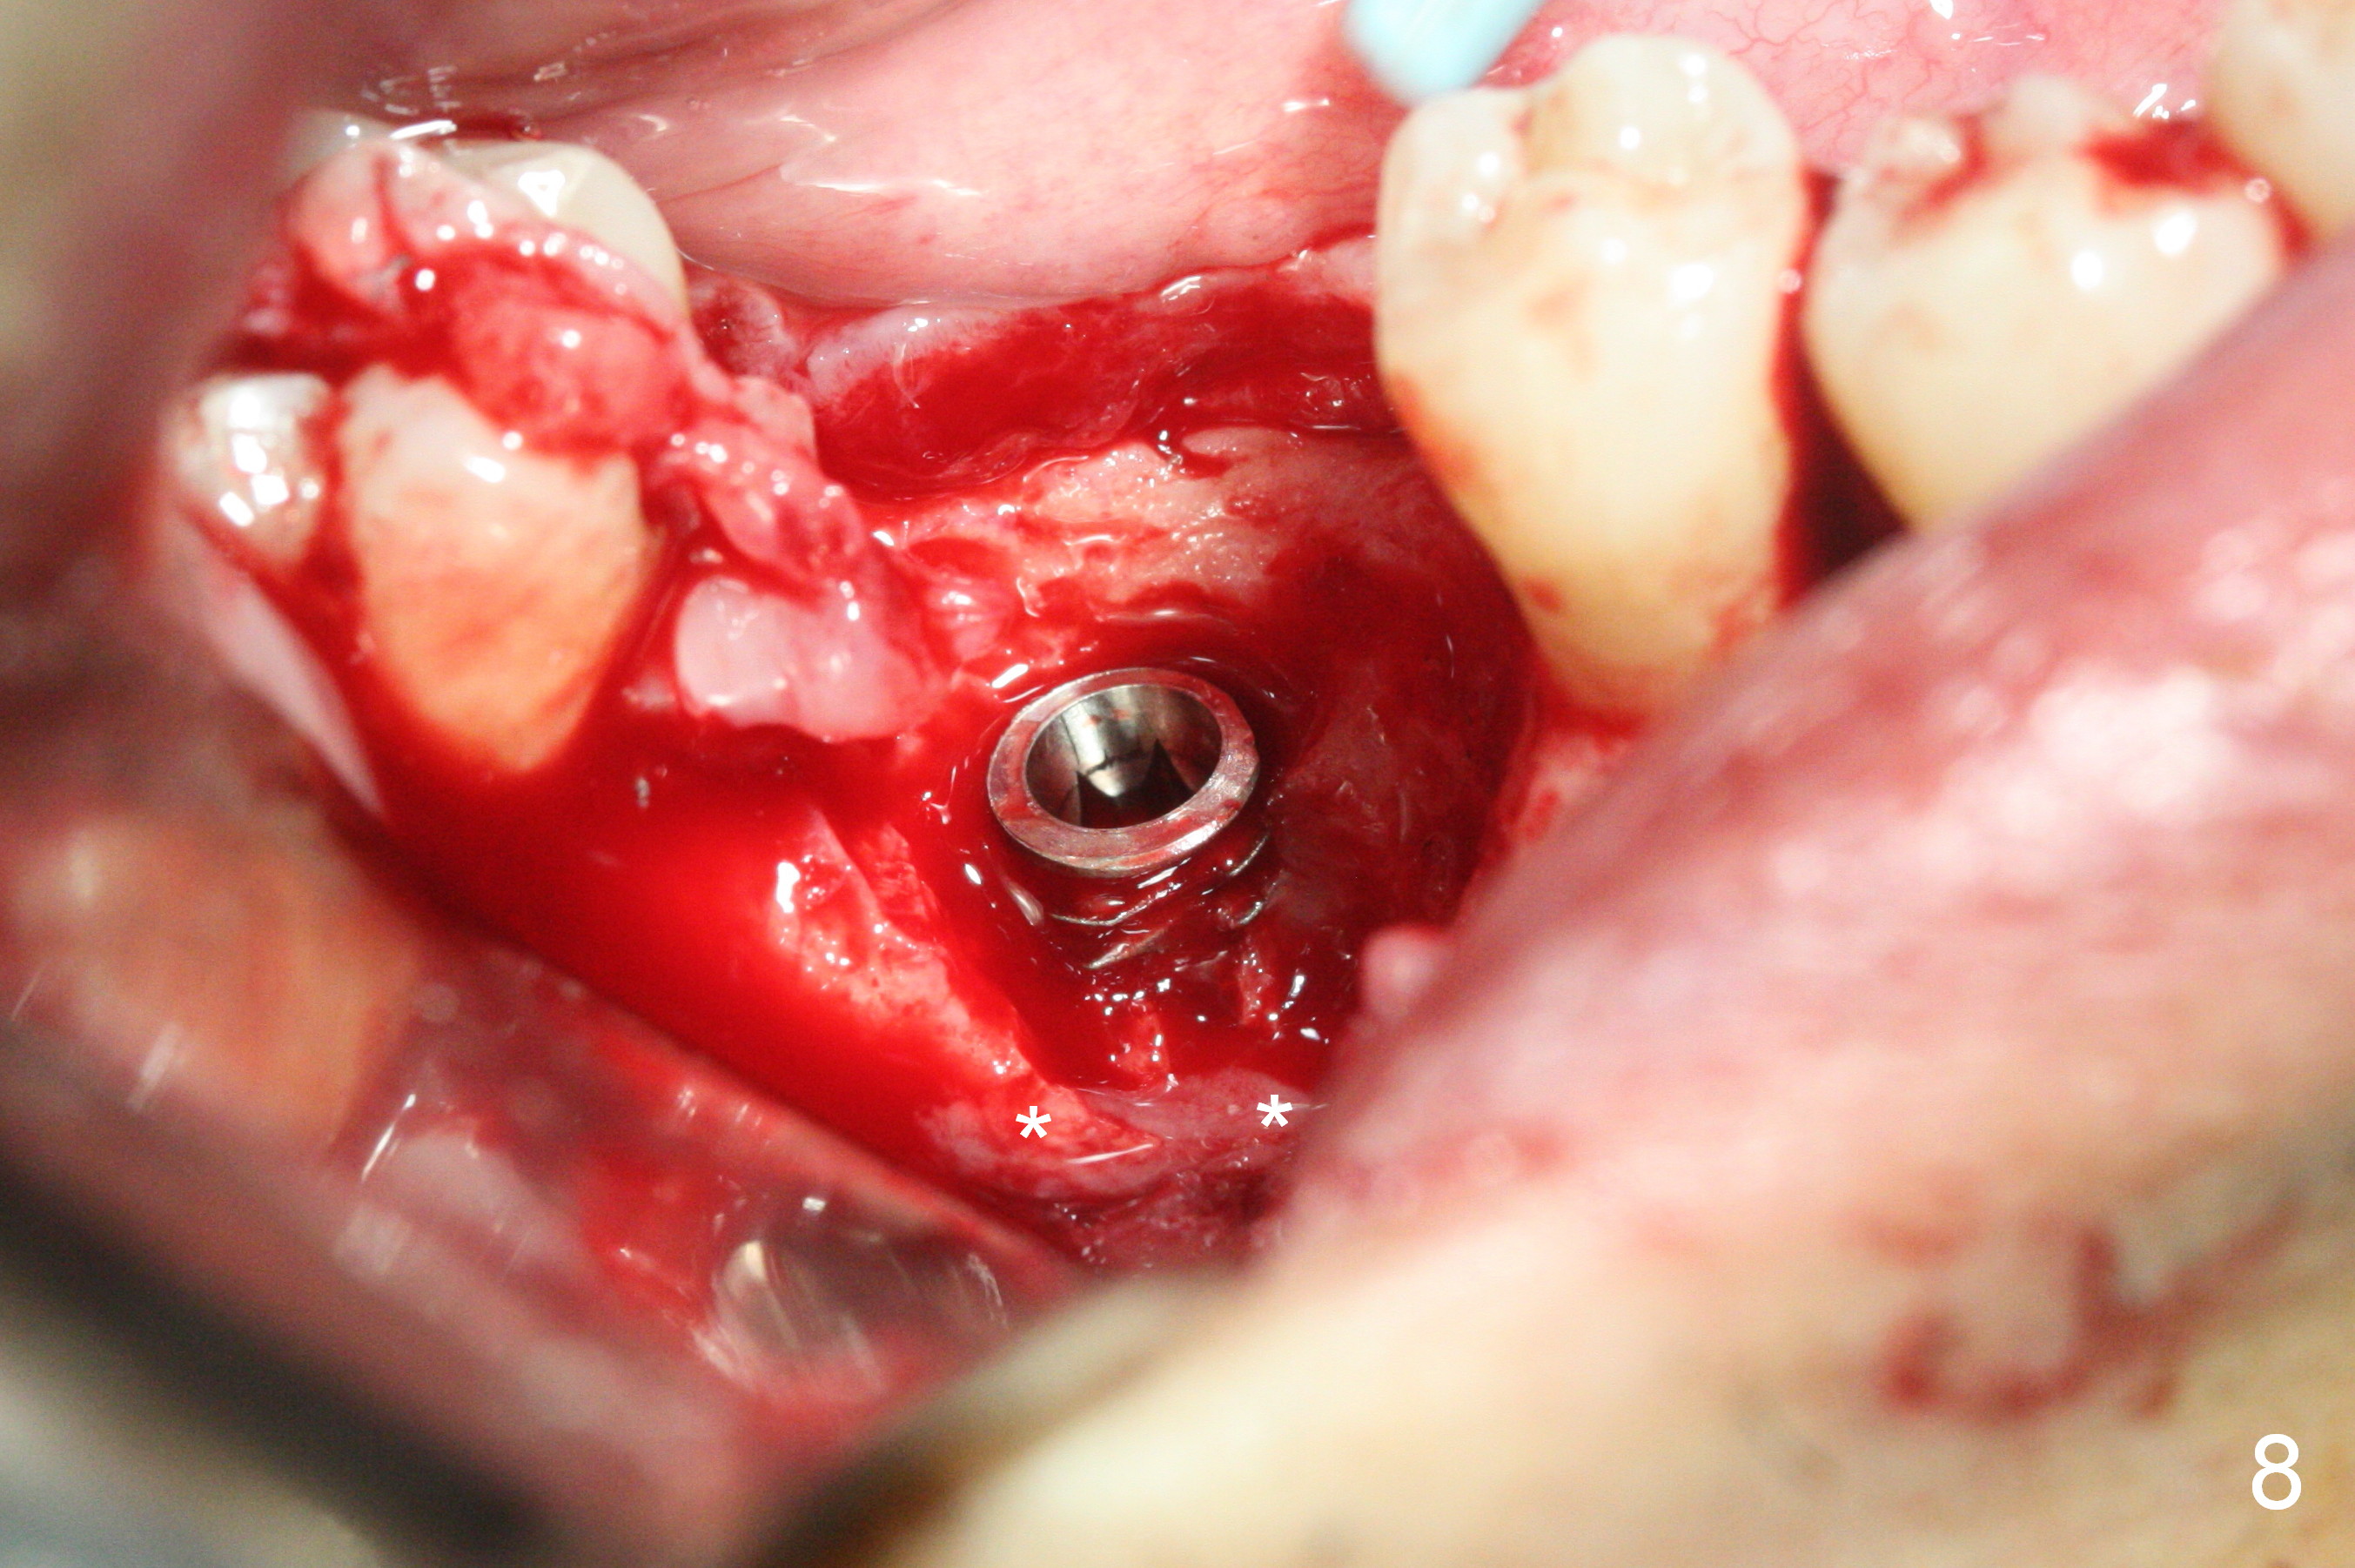

A 49-year-old man develops acute abscess of the lower right quadrant (Fig.3-5) secondary to periimplantitis at #30 (Fig.1,2,6). The latter is probably due to buccal placement (Fig.6 (*: buccal plate)). After removal of the infected implant, an osteotomy is established as lingual as possible using single drill modality (Fig.7 (4.3 mm Magic Drill after 1.6 mm pilot drill and Marking Bur, then Final Drill). With the single drill, the osteotomy does not shift buccally in spite of the lower buccal plate. A 5x9 mm IBS implant is placed lingually as planned (Fig.8 (>40 Ncm)), followed by an angled abutment (5 mm x 15° (4 mm)) (Fig.9 A). The buccal gap is filled with autogenous bone, allograft (.5-1.5 mm) and Osteogen (Fig.10 *), covered by resorbable and non-resorbable membranes. After suturing, periodontal dressing is applied.